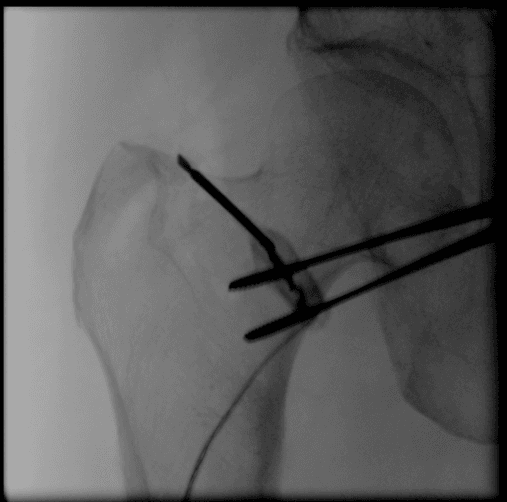

With only a 4 mm skin incision and a patented technique pioneered by our founder Dr. Ara Deukmedjian MD, pain nerves to the joint are targeted and permanently disconnected so our patients can enjoy long term pain-free movement.

A less invasive, state of the art treatment to permanently relieve piriformis syndrome symptoms by disconnecting the painful muscle from its attachment to the hip. The procedure was pioneered at Deuk Spine Institute in 2024 by Founding Neurosurgeon Dr. Ara Deukmedjian MD with the help of his son, Arias Deukmedjian.Â

Deuk Piriformis Muscle Release is a one-of-a-kind procedure offering the safest and most effective treatment of piriformis syndrome in the world. There is no hospitalization. Bleeding is minimal (a few drops) and recovery takes 30 minutes. A band aid is all that is needed for the 4mm incision. Most patients return to work the following day.